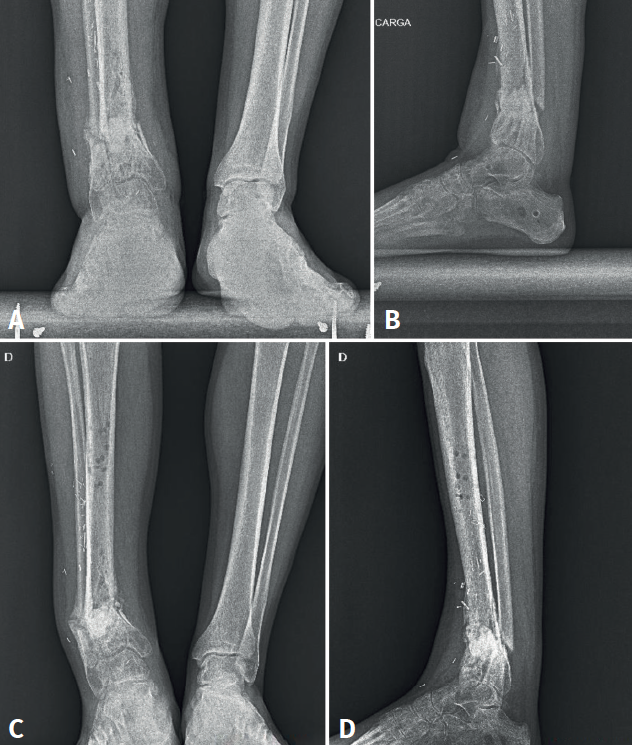

Figura 4. Radiografías A y B: deformidad del tobillo un mes tras la retirada del fijador externo; C y D: 5 meses tras la retirada.

El fijador se mantiene durante 5 meses y es retirado tras observarse consolidación parcial con puentes óseos en la TAC. Durante los meses siguientes se observa una deformidad progresiva en varo del miembro y una no consolidación de la fractura (Figura 4). Se realiza una gammagrafía que es compatible con pseudoartrosis. Finalmente, 1 año tras la fractura ingresa en el hospital por pseudoartrosis con sospecha de osteomielitis crónica.